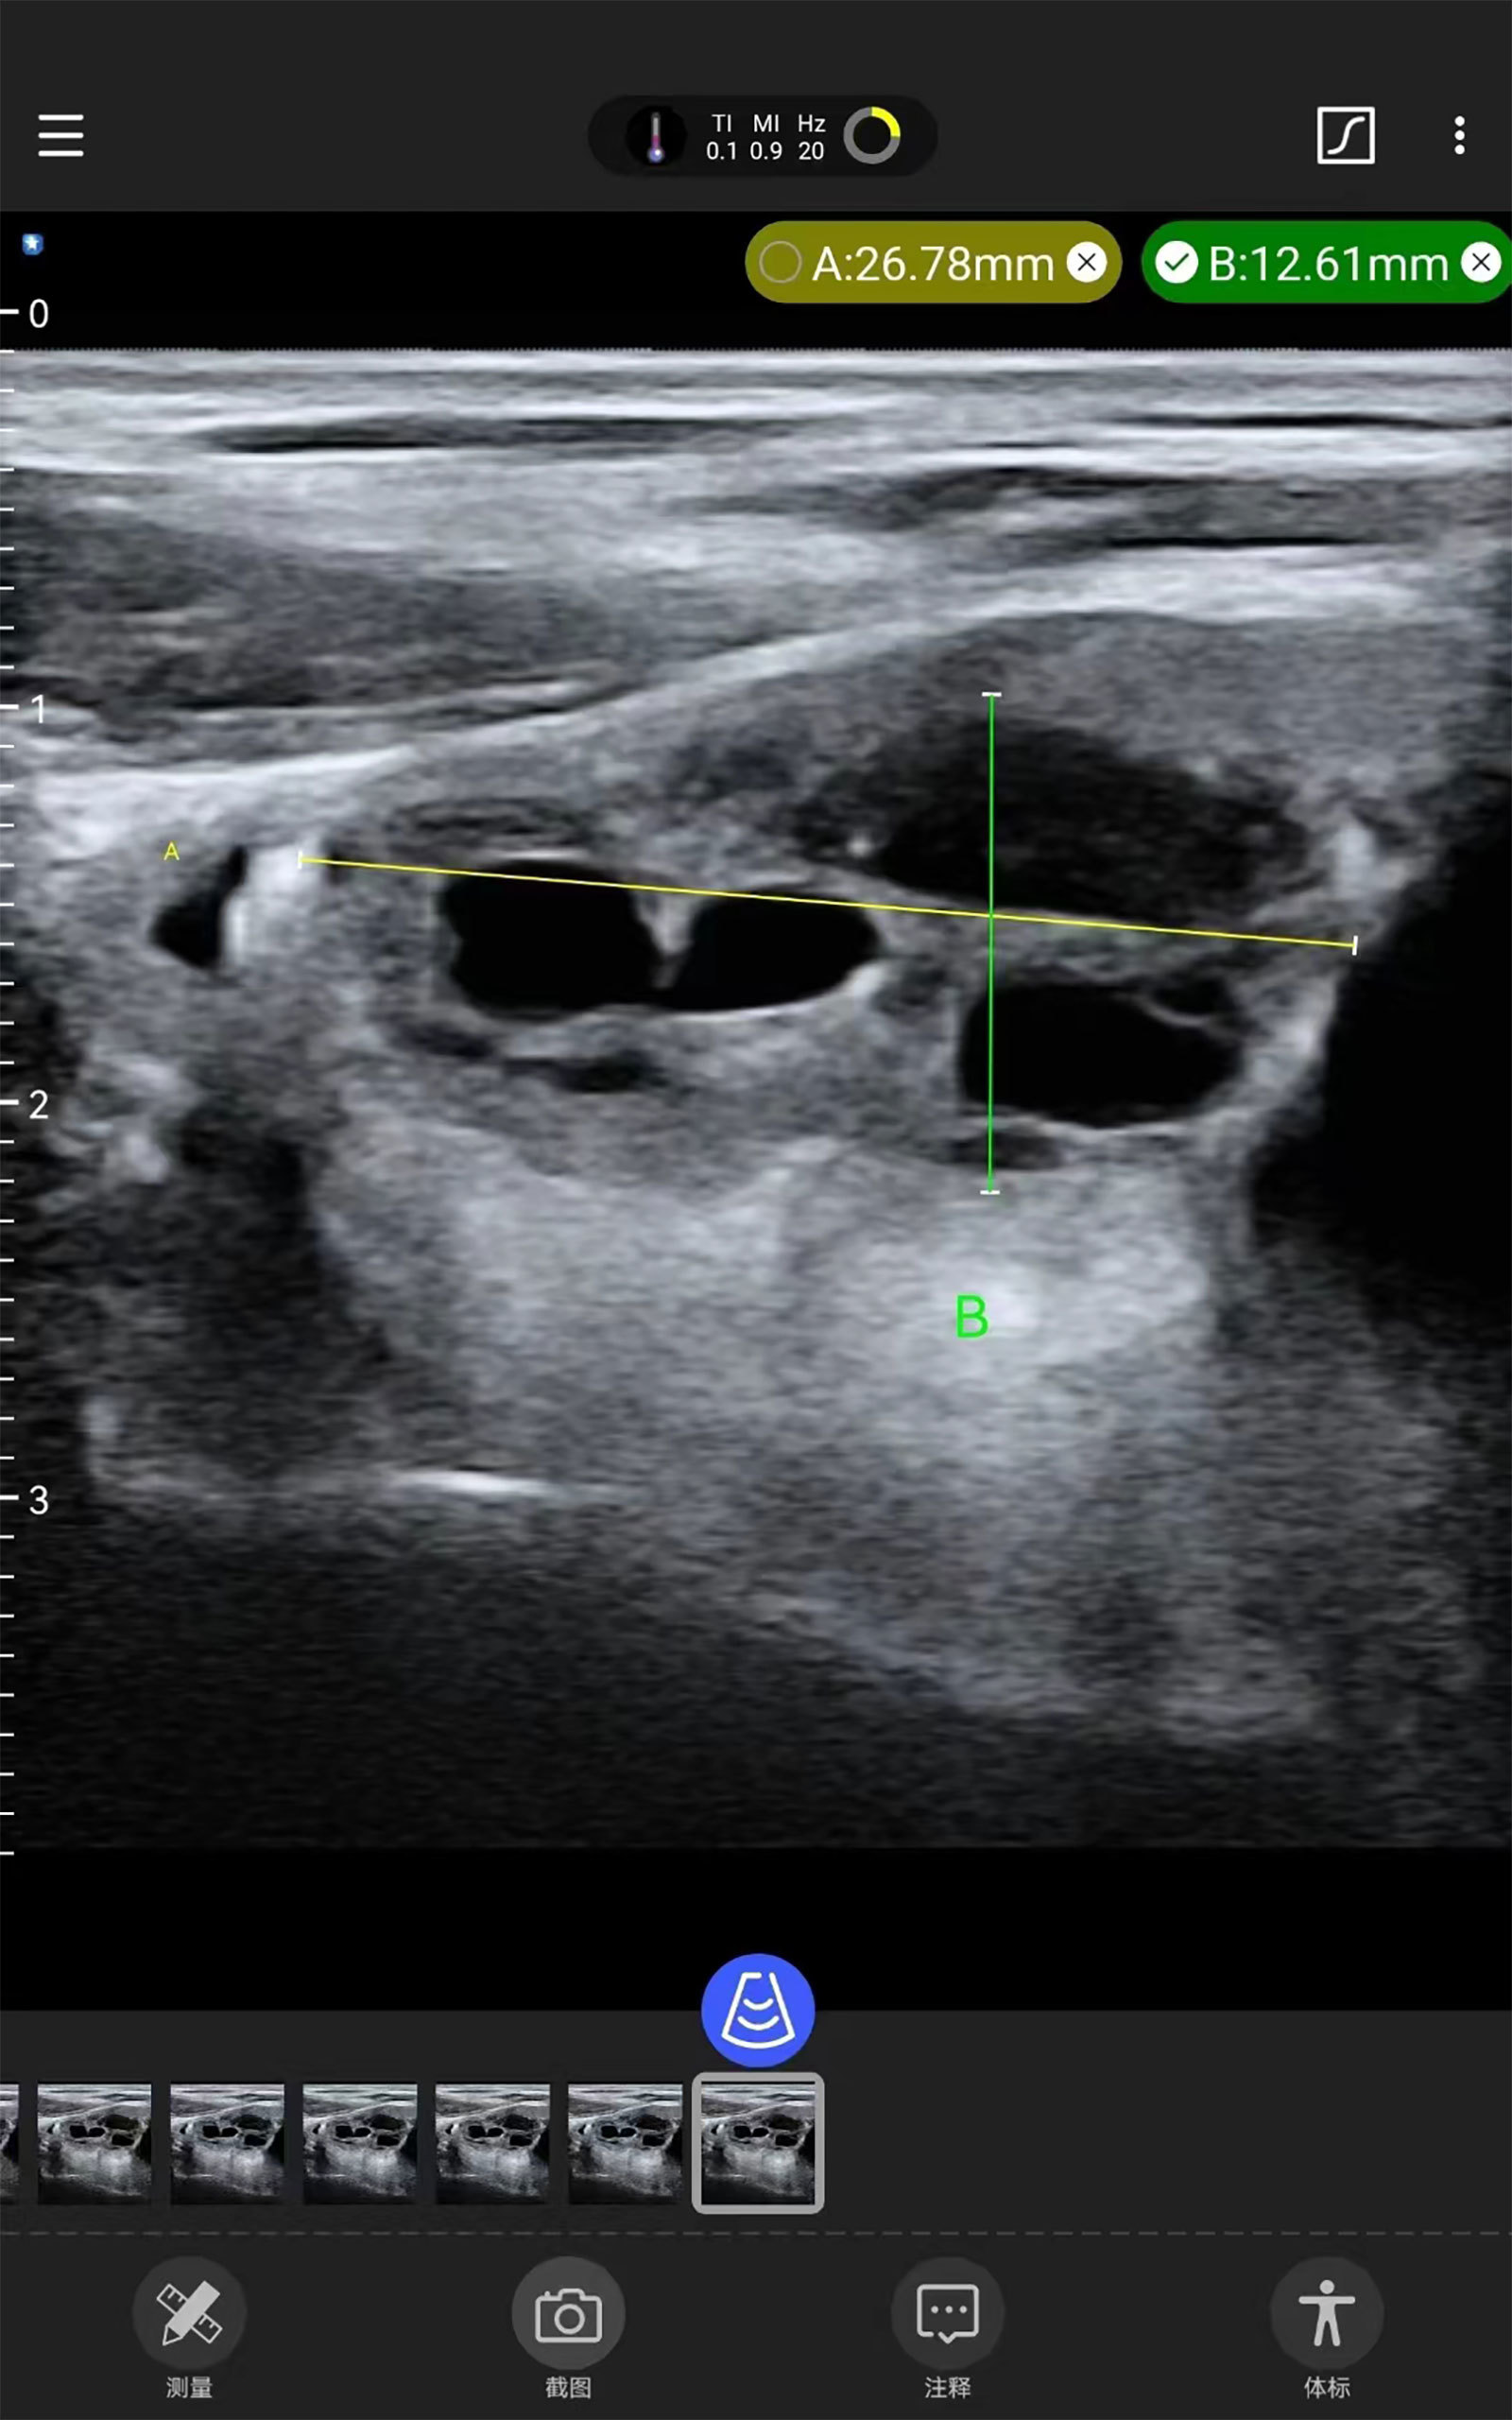

Tiroides Mama ( Guía de ablación por punción )

Galería de demostración